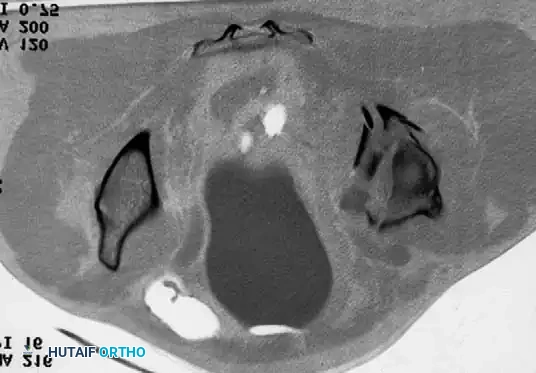

The femoral head is often partially resorbed due to inflammatory erosion or secondary osteonecrosis, and varying degrees of protrusio acetabuli are common.

Special handling of the limb is paramount. The osteopenic bone is highly susceptible to iatrogenic fracture. Retractors must be placed with extreme care; levering the femur anteriorly with a Hohmann retractor can easily fracture the anterior acetabular margin or the femoral neck.

Preparation of the femur is usually straightforward due to a widened medullary canal (Dorr Type C "stovepipe" femur), but the cortices are paper-thin and easily penetrated. The acetabulum is similarly soft, and the medial wall is easily breached during reaming.